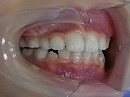

初診時

初診時より1年6カ月後 終了時(10歳9か月)